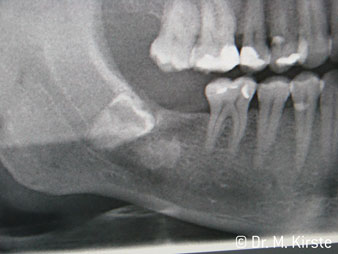

The 45° angle of the handpiece has been specially selected for its wide range of advantages. Colleagues who work in surgery, and for whom this handpiece was primarily developed, will soon appreciate the ability to work efficiently in very restricted spaces. In wisdom tooth extractions in particular (fig. 2) there is no need for large-scale spreading of the soft tissues in the cheek region (fig. 3). The design of the handpiece head combined with turning the head slightly during preparation allows work to be carried out quickly and safely in the retromolar region.

The professional design of the bearings inside the handpiece head guarantees quiet running of the bur; this makes for an impressively atraumatic cut in the separation of tooth and root (fig. 4-9).